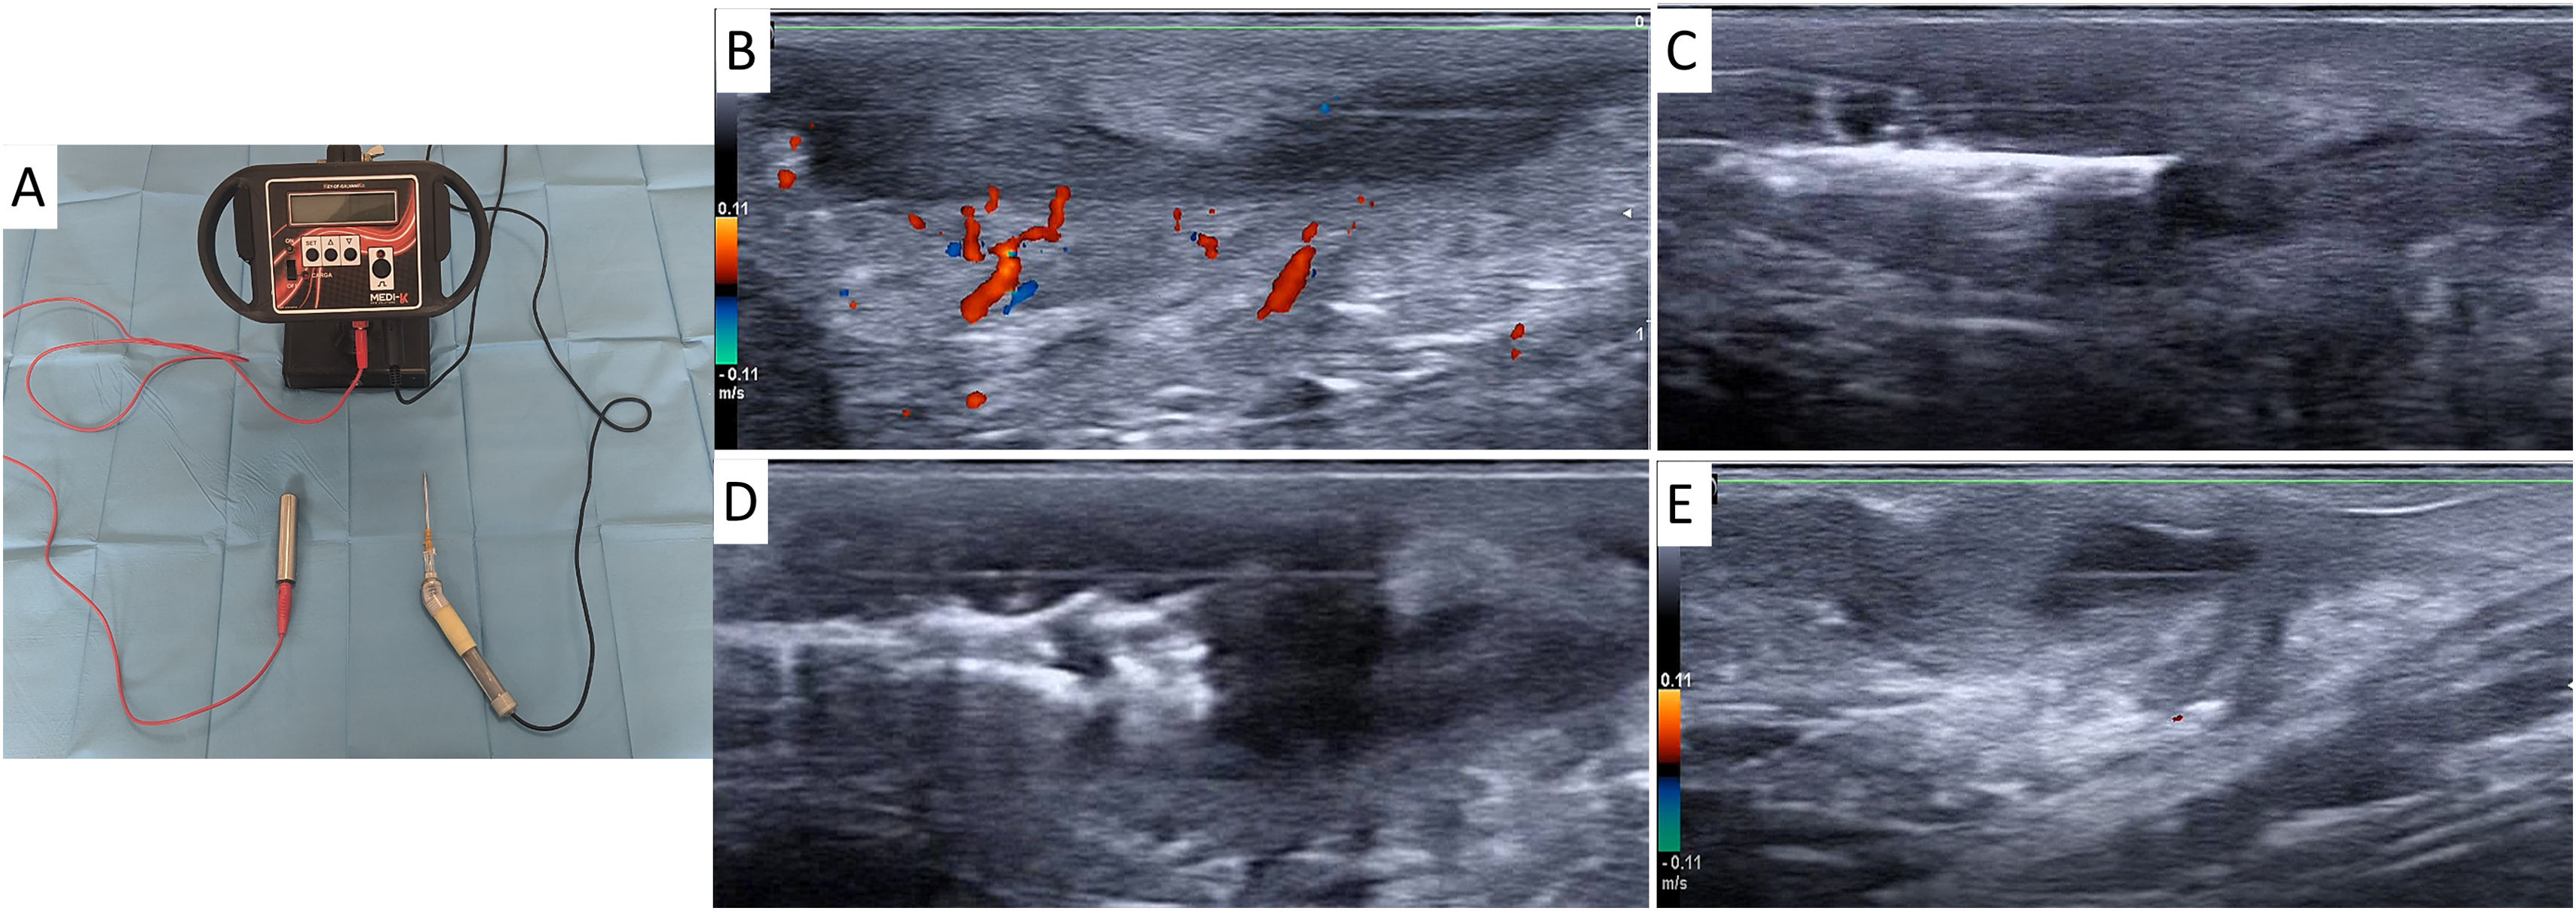

Procedure descriptionUltrasound-guided percutaneous galvanic current: Local tumescent anesthesia was administered in the area to be treated (100mL of saline solution, 2mL of 2% mepivacaine, 1mL of 0.5% bupivacaine with epinephrine, and 2mL of 1 molar bicarbonate). Subsequently, a 14 G Abbocath needle was inserted into the tunnel under ultrasound guidance and connected to the cathode of the CG Galvani-K® galvanic current generator (Fig. 2). While the patient held a manual anode, 5–10 cycles of GC were delivered at 5mA, continuous, uninterrupted, with constant intensity and duration of 5s. The Abbocath was mobilized within the lesion lumen to ensure contact with the roof, floor, and walls, being withdrawn from distal to proximal 1cm between cycles to achieve homogeneous current administration. A second GC cycle could be administered at week 4 if complete response was not achieved.

Galvani-K® device and ultrasound-guided procedure. (A) Galvanic current generator with integrated Abbocath catheter adapter and contact electrode. (B) HS inflammatory tunnel before treatment initiation with inflammatory hyperemia identified by Doppler. (C) Abbocath catheter inserted inside the tunnel under ultrasound guidance. (D) Hyperechogenic sclerosis line after administration of galvanic current and withdrawal of the Abbocath catheter. (E) Week 12 into therapy: disappearance of inflammatory hyperemia on Doppler signal, reduction in longitudinal diameter, and decrease in perilesional edema.